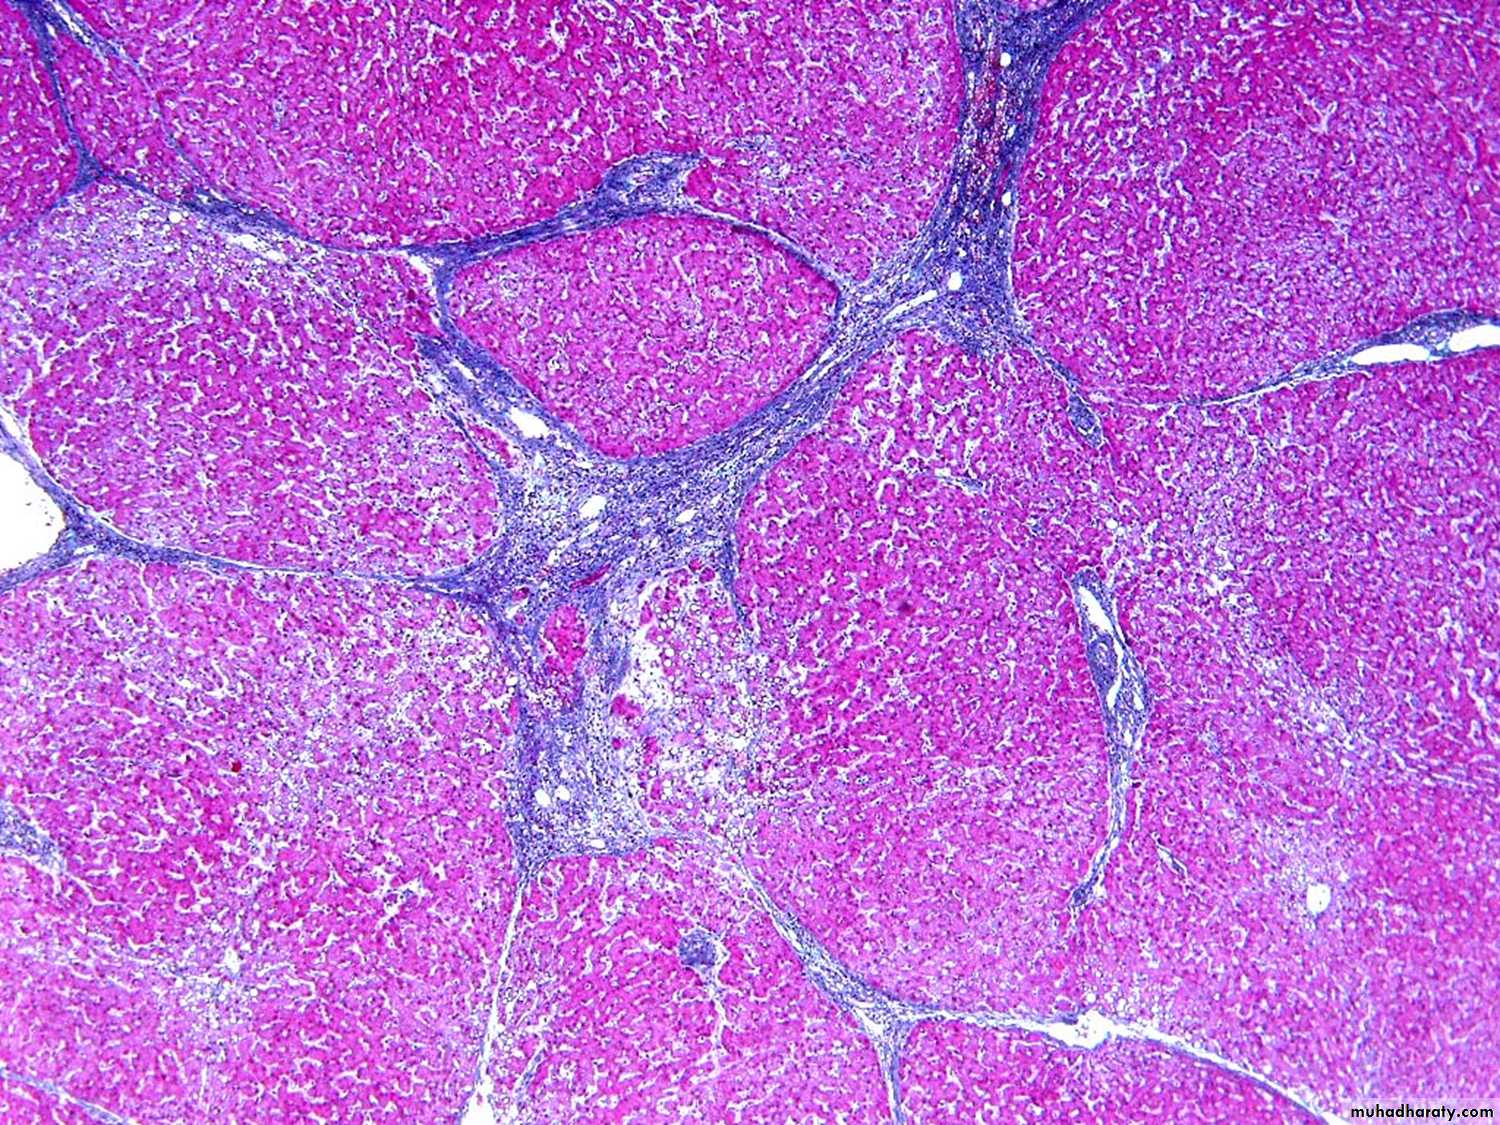

• Histopathological Features of cirrhosis:

The regenerative nodules of hepatocytes are surrounded by fibrous connective tissue that bridges between portal tracts

CIRRHOSIS, TRICHROME STAIN